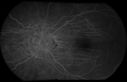

Choroidal Folds1147 viewsChoroidal Folds imaged during angiography and the corresponding OCT